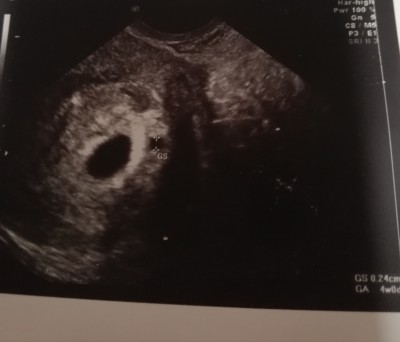

Günaydın arkadaşlar. Ben dün kahverengi akıntıyl

a acile gittim. 21 inde kontorülüm vardı 1 kese görülmüştü dün acilde 2 kese görüldü ama biri diğerine göre küçük baya. Başına gelen var mı gelişip öbürüne yetişir mi acaba..

Gebelik haftası 6+4